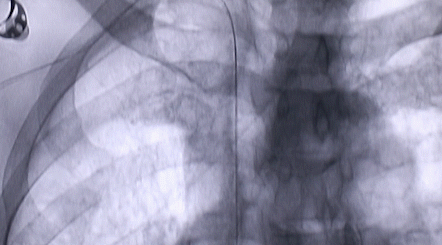

1月12日,西安國(guó)際醫(yī)學(xué)中心醫(yī)院心臟外科郭穎強(qiáng)主任團(tuán)隊(duì)成功為一名腹主動(dòng)脈閉塞、右側(cè)腎動(dòng)脈閉塞、左側(cè)腎動(dòng)脈重度狹窄、腹壁淺表動(dòng)脈側(cè)支循環(huán)形成、高血壓病3級(jí)(極高危組)合并閉塞性周圍動(dòng)脈粥樣硬化、急性腎功能不全的老年患者實(shí)施腎動(dòng)脈球囊擴(kuò)張 腎動(dòng)脈支架植入術(shù) 動(dòng)脈血栓抽吸術(shù) 髂動(dòng)脈開通術(shù),治好了困擾患者多年的頑固性高血壓?;颊吣壳翱祻?fù)良好,將于近日出院。

按照術(shù)前制定的方案,郭穎強(qiáng)主任和楊金保博士首先嘗試開通閉塞的右腎動(dòng)脈,但由于血栓機(jī)化、鈣化嚴(yán)重,右腎動(dòng)脈難以開通。遂謹(jǐn)慎擴(kuò)張狹窄的左腎動(dòng)脈,并成功植入一枚支架。之后經(jīng)過反復(fù)旋磨、抽吸,順利開通髂動(dòng)脈,但腹主動(dòng)脈閉塞段仍難以擴(kuò)通。此時(shí),患者居高不下的血壓很快恢復(fù)到正常水平。

經(jīng)過3個(gè)半的奮戰(zhàn),最令張大伯頭疼的頑固性高血壓終于恢復(fù)了正常。術(shù)后當(dāng)日,張大伯便下床活動(dòng),次日復(fù)查腎功能,尿素氮、肌酐已基本恢復(fù)正常。